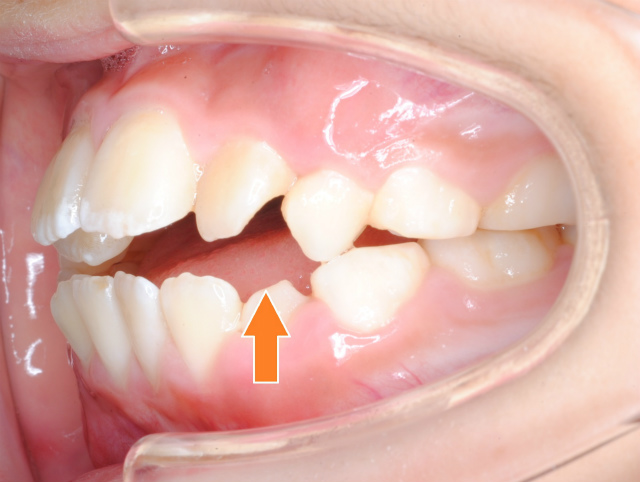

舌の側面が臼歯に被さって歯並びに作用してしまう。左側臼歯が前方に傾斜している様子